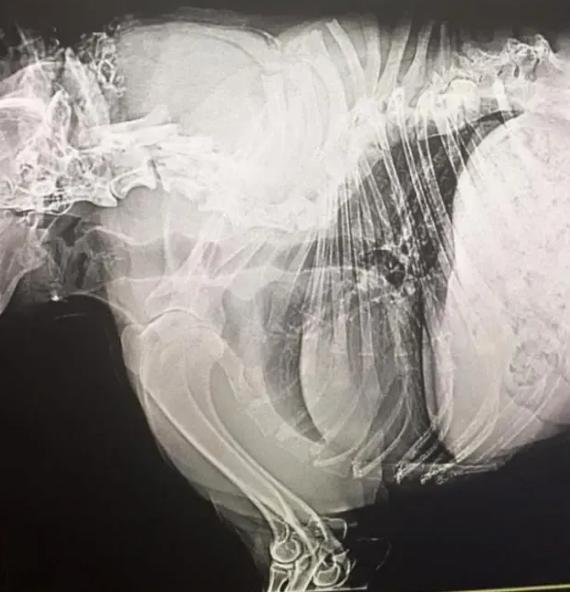

患者的脊柱比正常的貓狗要短,且是傾斜的,它有頭有尾,可能會沒有尾巴,頭部直接連接身體,看上去就是沒有脖子。

身體的原因,導致它們的內臟全部擠壓在一起,有多難受我們不得而知,但進食的時候無法彎腰,生活基本無法自理,需要靠主人幫助,想想也是挺痛苦的。